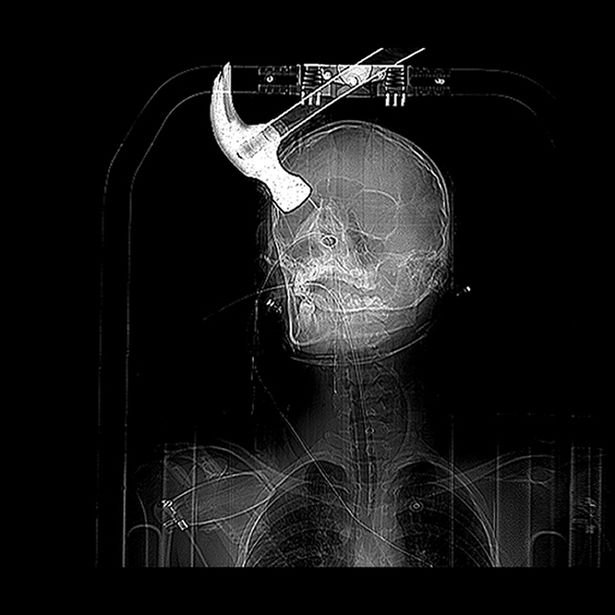

Connor Huntley foi encontrado por médicos com um martelo ainda incorporado em sua cabeça, depois de Joseph Williams, seu colega de quarto, ligar para as autoridades e confessar o terrível ataque.

A vítima teve a sorte de sobreviver ao ataque traumático, mas agora sofre de epilepsia e não é mais capaz de ser independente para realizar suas tarefas.